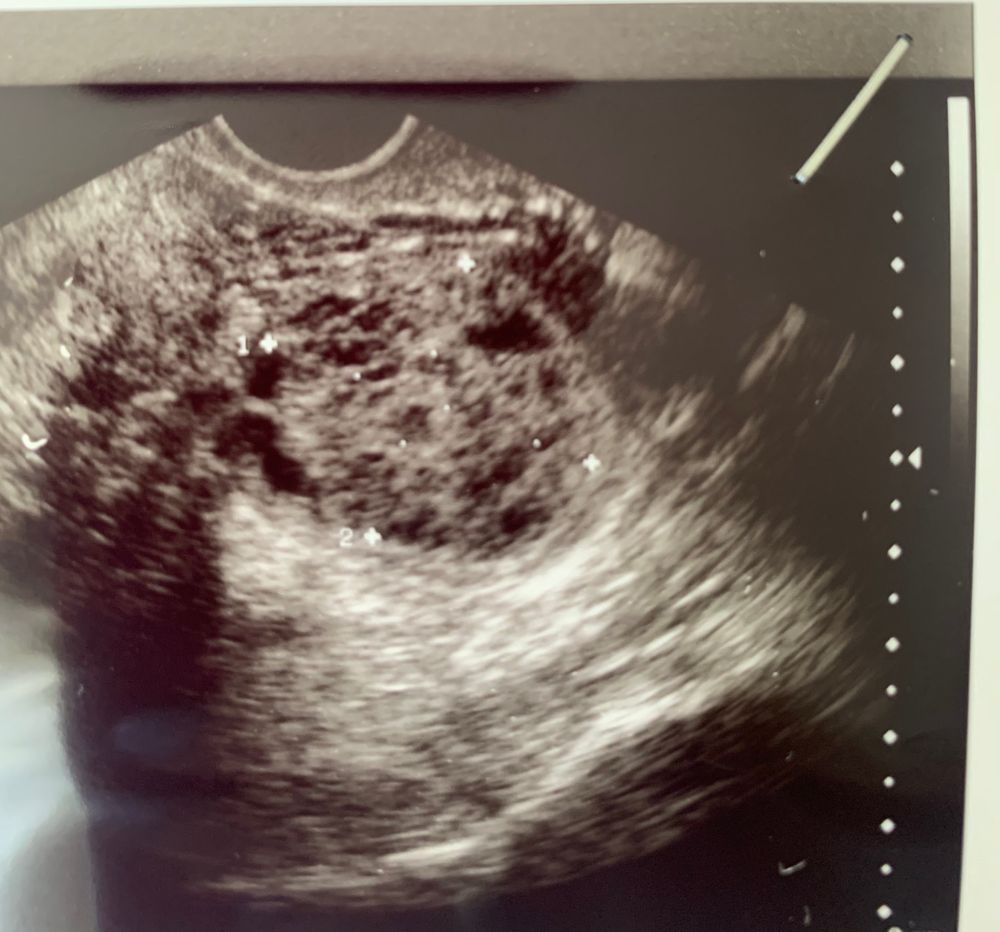

Вот так выглядит киста яичника,при чем у меня было сразу в обоих Я в цикле, у Вас скорее всего ЖТ.

TatyanaGS, ну моя по заключению геморрагическая (с кровью). Но она может же быть от фолликулярной или от кисты ЖТ... не расстраиватесь пока!!! Верьте в чудо, помните мою историю!!! Слишком уж у нас много общего)))